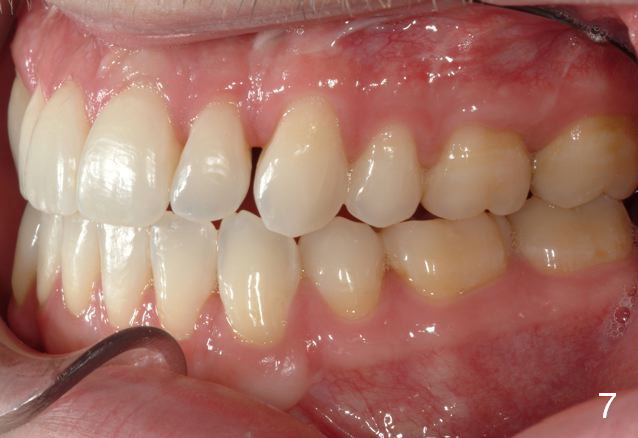

Final photos are taken on 03/23/2016. Mid face deficiency improved, now just a hint (Fig.3). Before (Fig.4,10) and after (Fig.5-9) occlusal adjustment of the canines.